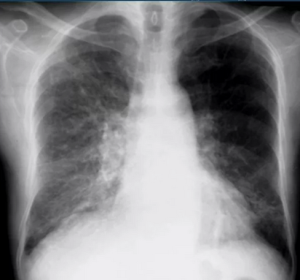

В соответствии с современными клиническими рекомендациями, диагностика ИЗЛ требует проведения мультидисциплинарного консилиума с участием врачей пульмонолога, рентгенолога, ревматолога и патологоанатома. Компьютерная томография высокого разрешения (КТВР) легких является “золотым стандартом” для получения подробных изображений легочной паренхимы и выявления паттерна, характерного для ИЗЛ [14]. Компьютерная томография высокого разрешения легких имеет важное значение для диагностики ИЛФ, выявляя специфические закономерности, такие как обычная интерстициальная пневмония [15].

Механизмы, лежащие в основе патогенеза ЛФ, включают различные клеточные взаимодействия. Будущие исследования должны быть направлены на выявление новых звеньев патогенеза. Для эффективного лечения ПФЛ решающее значение имеет ранняя и точная диагностика. Большие надежды связаны с открытием и применением новых биомаркеров для выявления заболевания на ранних стадиях, для оценки замедления прогрессирования заболевания. Компьютерная томография высокого разрешения остается одним из основных методов оценки ответа на лечение и мониторинга прогрессирования заболевания. Антифиброзная терапия ЛФ (нинтеда- ниб и пирфенидон) является общепризнанной и общепринятой. Следует рассмотреть комбинацию методов лечения, нацеленных на клеточные взаимодействия, в частности с использованием антифиброзных препаратов клеточной и генной терапии. Использование современных методов диагностики и комплексного терапевтического подхода позволит добиться существенного прогресса в понимании и лечении ПФЛ.